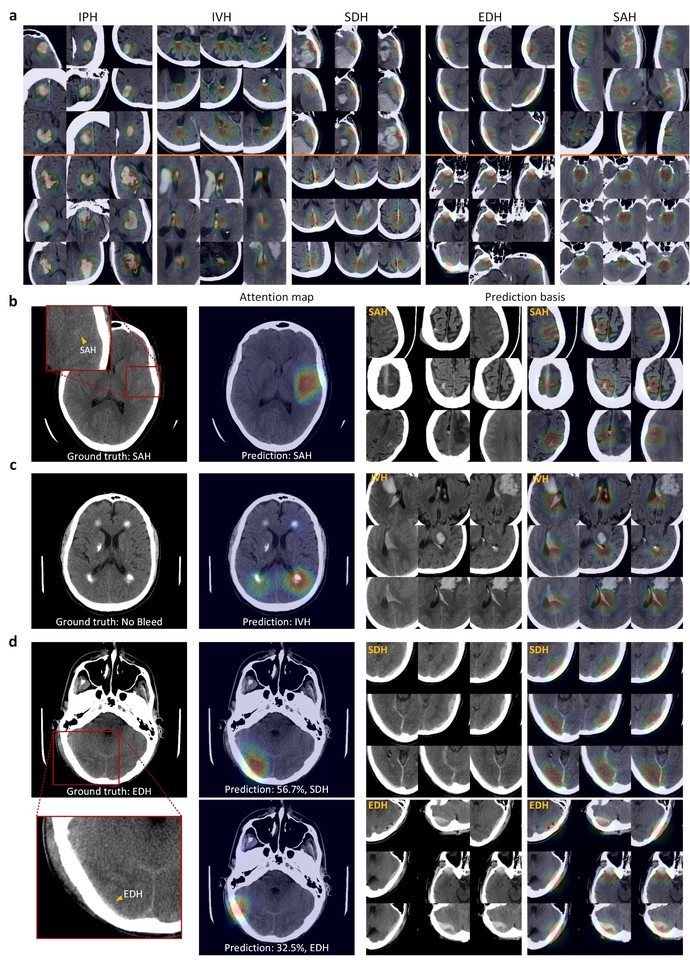

Also noteworthy is our creation of an “explainable” prediction basis. Although our platform provides quantitative hemorrhage localization by attention maps, these do not fully explain the reasons for the decisions made by the model. We found that our models learned invariant features of various appearances & locations of ICH, so we incorporated retrieval of these representative training images – which contain significant features relevant to each test image - into our platform as a supplement to the attention maps, thus providing the user with an explanation for the model’s predictions [Fig 5].